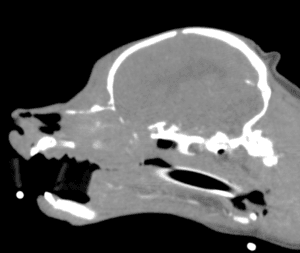

腫瘍科外来

犬・猫のリンパ腫、乳腺腫瘍、肥満細胞腫などの腫瘍性疾患の診察と治療を行います。